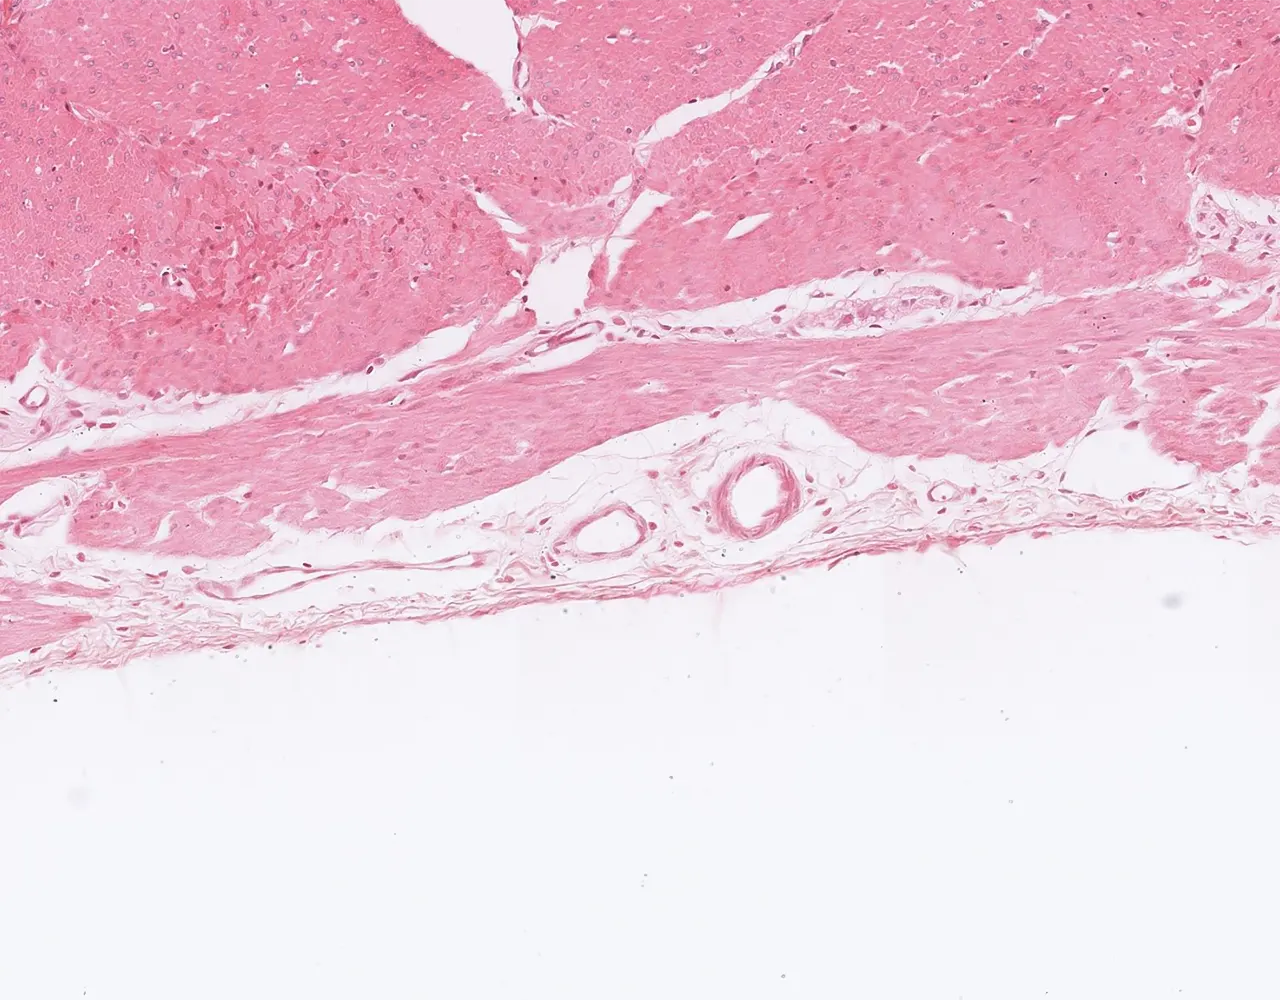

- The wall of the stomach is composed of four layers, from the innermost to the outermost: mucosa, submucosa, muscularis propria, and serosa.